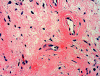

Histopathology: Panel B is taken at the periphery of the tumor where a well circumscribed margin is demonstrated. The tumor has rich vascularity and a hypocellular stroma. However, increased stromal cellularity is present in some areas.  Hyalinized blood vessels and a sclerotic to edematous stroma are well demonstrated in Panel C. Also present are a few lymphocytes clustering around blood vessels. The sclerotic stroma with edema and sparse lymphocytic infiltration is demonstrated in Panels D and E. The bland cytologic features are shown in Panel F.

The stromal cells possess a bland, oval or elongated nuclei and either scanty, amphophilic cytoplasm with ill-defined margins or eosinophilic, tapered cytoplasm with better delineated cell borders. Intranuclear inclusions and longitudinal nuclear grooves are common in the spindle cells. Epithelioid mesenchymal cells with globoid eosinophilic cytoplasm and a single nucleus or occasional multiple, round nuclei may be present. Mitotic figures are characteristically rare or absent. The cellularity is quite variable and is somewhat related to the vascularity. In most cases, the spindled and epitheloid cells proliferate in a haphazard arrangement. In the more cellular cases, spindled cells form loosely organizing fascicles. Tumor cells may aggregate or form masses around blood vessels and those that are close to blood vessels may have a myoepithelial appearance. The vascular component of the tumor consists of small to medium-sized, rounded, curvilinear, non-branching, and thin-walled vessels. Perivascular fibrosis or sclerosis is a feature detected to some degree in all cases 11.  Mature adipocytes can be sparsely scattered within the neoplasm and, in rare cases, adipose cells predominate; such tumors have been classified as the “lipomatous” variant of angiomyofibroblastoma 8 by some investigators. Strong and diffuse immunoreactivity for both desmin and vimentin is demonstrated in practically all cases. Only a minority of cells in some cases show positive immunoreactivity for either smooth muscle actin or pan-muscle actin 1, 12, 13, 14 , 15. Tumor cells are negative for S-100 protein, cytokeratin, collagen type IV, CD 68 and myoglobin 16. The few cases examined ultrastructurally have shown fibroblastic features in most cells, with a minority showing myofibroblastic differentiation 1, 12, 14.